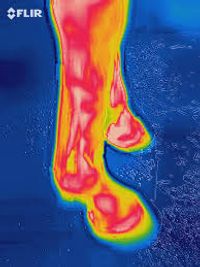

Vasculaire doorbloeding, spieren bij mens en dier en nachtzicht toepassingen.